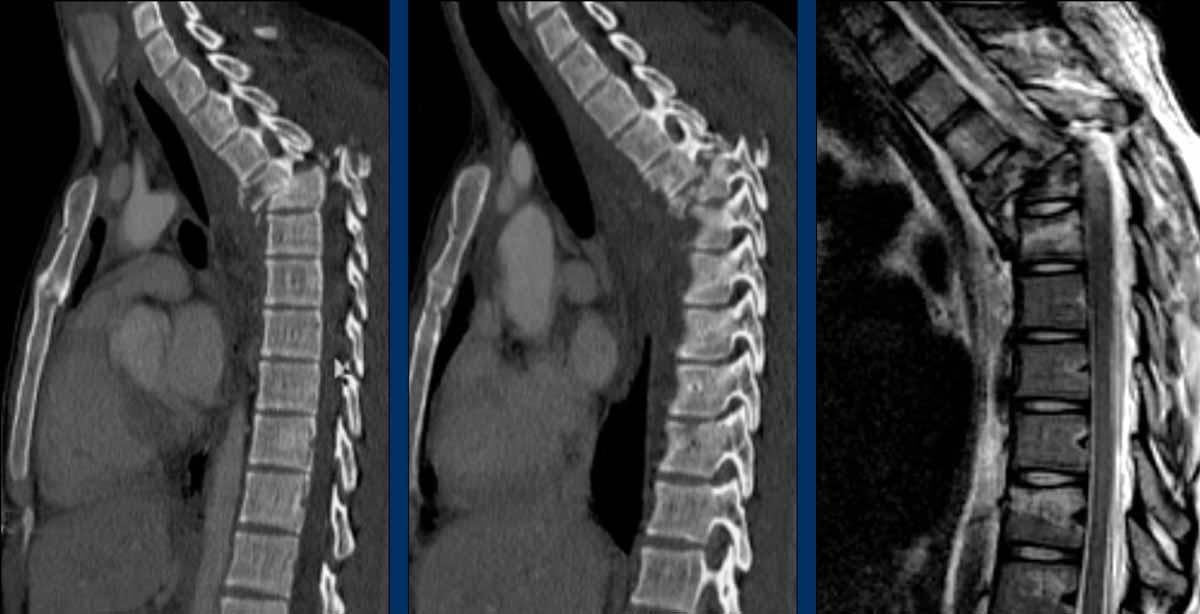

Findings

- The most severe level is L4/5 with dislocation (dotted lines)

- Facet fractures at L4 (arrows).

- A4 burst fracture (circle).

Conclusion:

Injury type C + A4 at L4/5.

Continue with the next stack of images to classify level L2…

Scroll through images.

What is the highest AO-level?

- No dislocation ( no C type).

- Mainly horizontal fractures of spinous processus at multiple levels (B-type).

- Split fracture L2 (type A2).

Conclusion

Injury type B2 + A2 at level L2.

The combination of these fractures make it difficult to comprehend what exactly has happened.

The AO spine classification is only designed to classify these injuries as simple as possible.